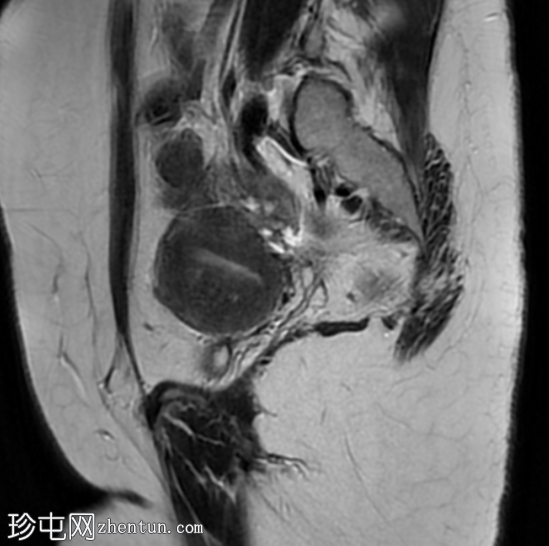

轴位

T2加权像

双角子宫,有两个子宫角和一个宫颈(单颈双角子宫)

左角局灶性前壁腺肌症,前壁交界区边界不清,肌层内可见多个高信号灶

两个小的间质性肌瘤和一个大的浆膜下肌瘤

该病例表现为双角子宫单宫颈(双角单颈子宫),左侧单侧局灶性子宫角腺肌症,以及多发性子宫肌瘤。